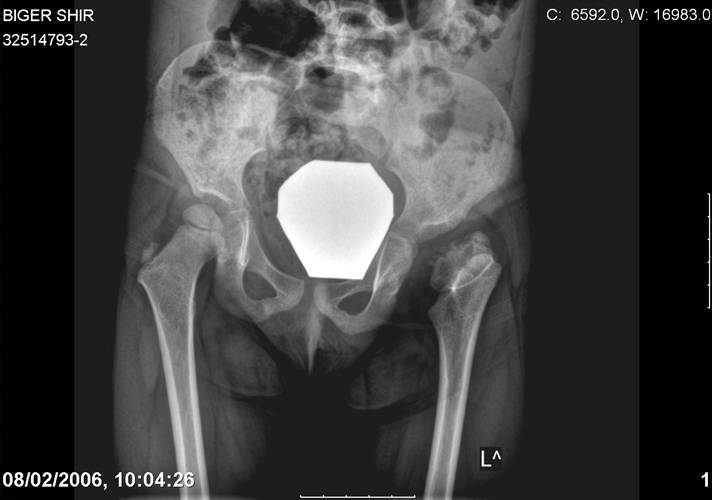

Navernoe Dega

Chto by ne byt goloslovnym posilau vam svoi sluchai gde sdelal vse chto napisal vyshe